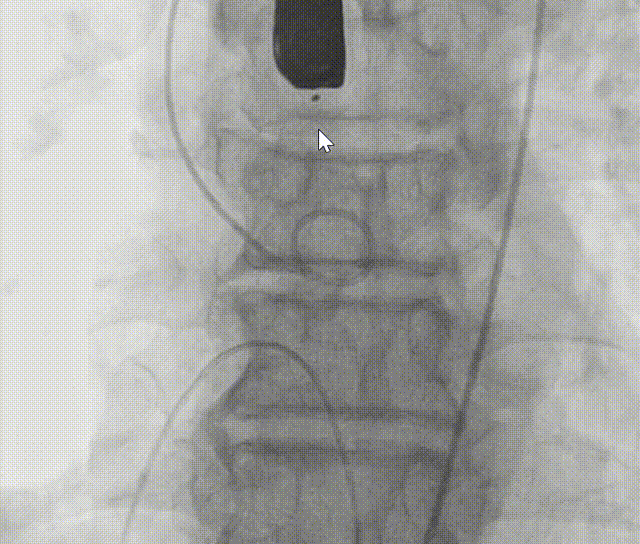

+1cc体积后扩。

图片